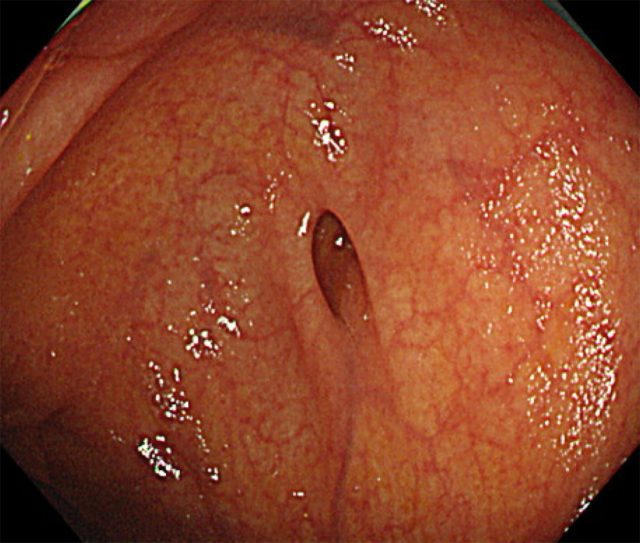

大腸憩室症

腸の壁が弱くなり、袋状の「憩室」が複数できる状態のことです。

多くの場合は無症状ですが、憩室に炎症が起きると「大腸憩室炎」、血管が破れると「大腸憩室出血」といった合併症を起こすことがあります。